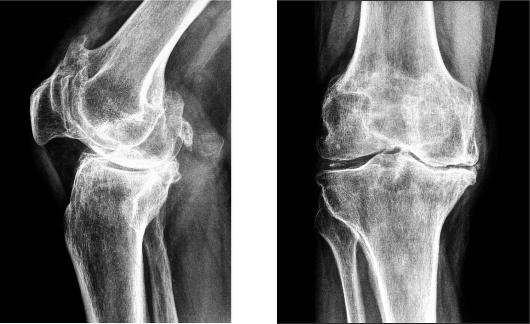

- МРТ — для оценки степени поражения мягких тканей;

- рентгенография — для оценки состояния твердых тканей и дифференциации диагноза, исключая артроз и другие аналогичные дегенеративные суставные заболевания.

Сочетание этих методов способствует более точному определению типа артропатии и выбору адекватного лечения.